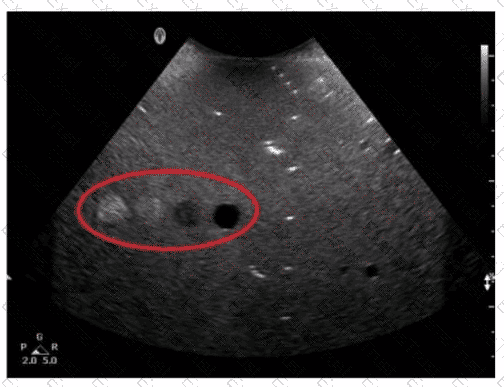

Question 26

Which resolution can be evaluated in the area indicated by the red oval in this image of a tissue-equivalent phantom?

Options:

A.

Elevational

B.

Contrast

C.

Lateral

D.

Axial

Question 50

Which target group in this image of a tissue-mimicking phantom is used to evaluate axial resolution?

Option A

Option B

Option C

Option D